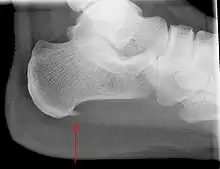

An incidental finding associated with this condition is a heel spur, a small bony calcification on the calcaneus (heel bone), which can be found in up to 50% of those with plantar fasciitis.[6] In such cases, it is the underlying plantar fasciitis that produces the heel pain, and not the spur itself.[13] The condition is responsible for the creation of the spur though the clinical significance of heel spurs in plantar fasciitis remains unclear.[12]

Imaging

Medical imaging is not routinely needed. It is expensive and does not typically change how plantar fasciitis is managed.[16] When the diagnosis is not clinically apparent, lateral view X-rays of the ankle are the recommended imaging modality to assess for other causes of heel pain, such as stress fractures or bone spur development.[7]